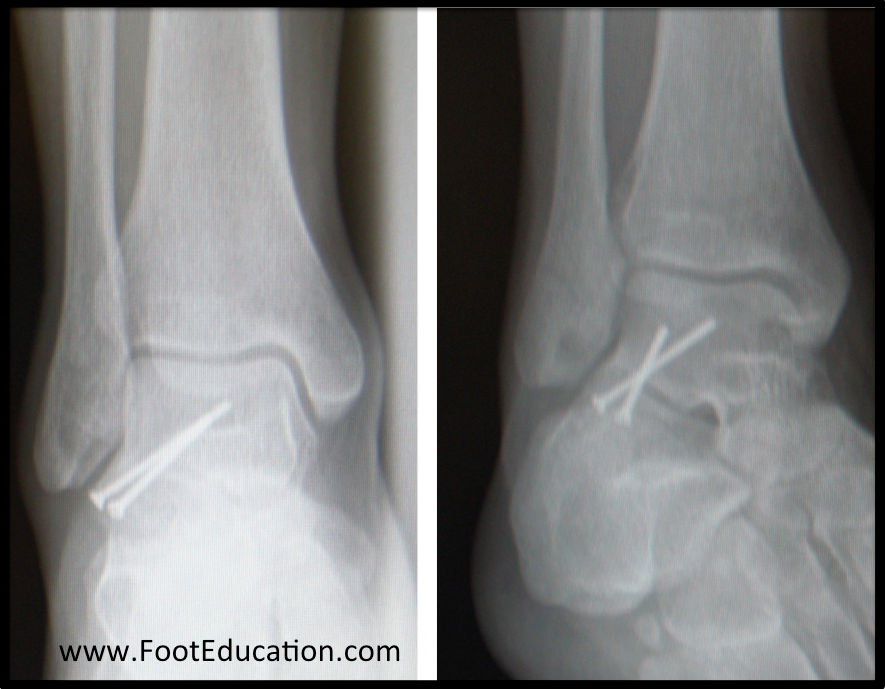

From footeducation.com

Lateral Talar Process Fractures FootEducation Can You Break Your Talus Bone A talus fracture is a serious injury that can cause pain, swelling, and difficulty walking. A talus fracture is a broken bone in your ankle. An unstable talus fracture occurs when a piece of bone is displaced from its attachment. Learn about the types, diagnosis, treatment, and recovery of a talus fracture. It can result from a fall, a car. Can You Break Your Talus Bone.